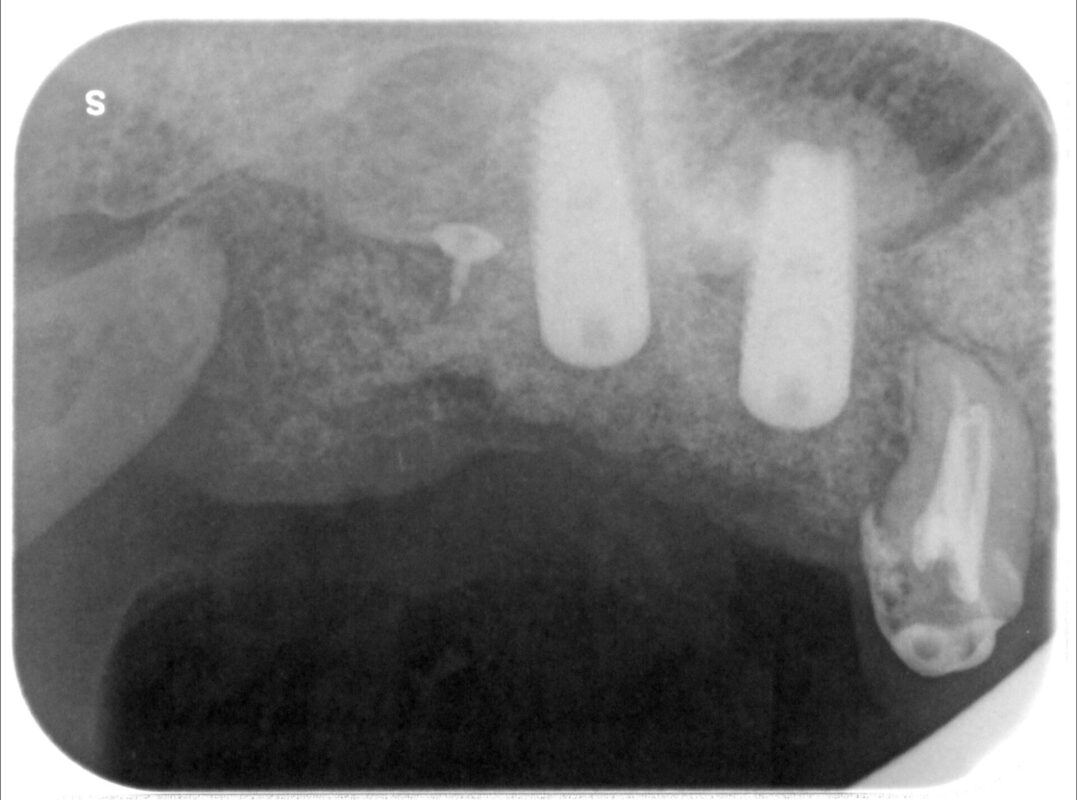

5カ月経過後CTによる骨の増加を確認し、インプラント治療となりました。

まだ骨の高さ不足のため、今回は上部からの骨移植を行っています。(ソケットリフト)

吸収性メンブレンを用いてさらなる骨造成も行っています。

インプラント処置直後

インプラント上端に盛り上がった骨が確認できます。

ここから約半年間インプラントと骨との結合を待ちます。